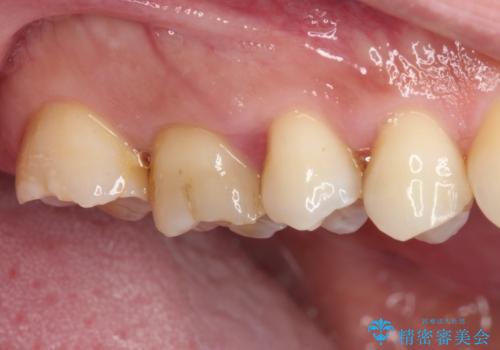

- 奥歯の間から出血するとのことで来院された患者様です。

口腔内は非常にきれいで、定期的に歯科医院でのクリーニングも行っているとのことでしたが、歯肉からの出血が一向に解決しない状態でした。

奥歯の歯間部の歯肉が炎症で赤黒くなっており、歯周ポケットを検査したところ、6-8mm(正常では3mm以下)であり、外科処置が適用となる状態でした。